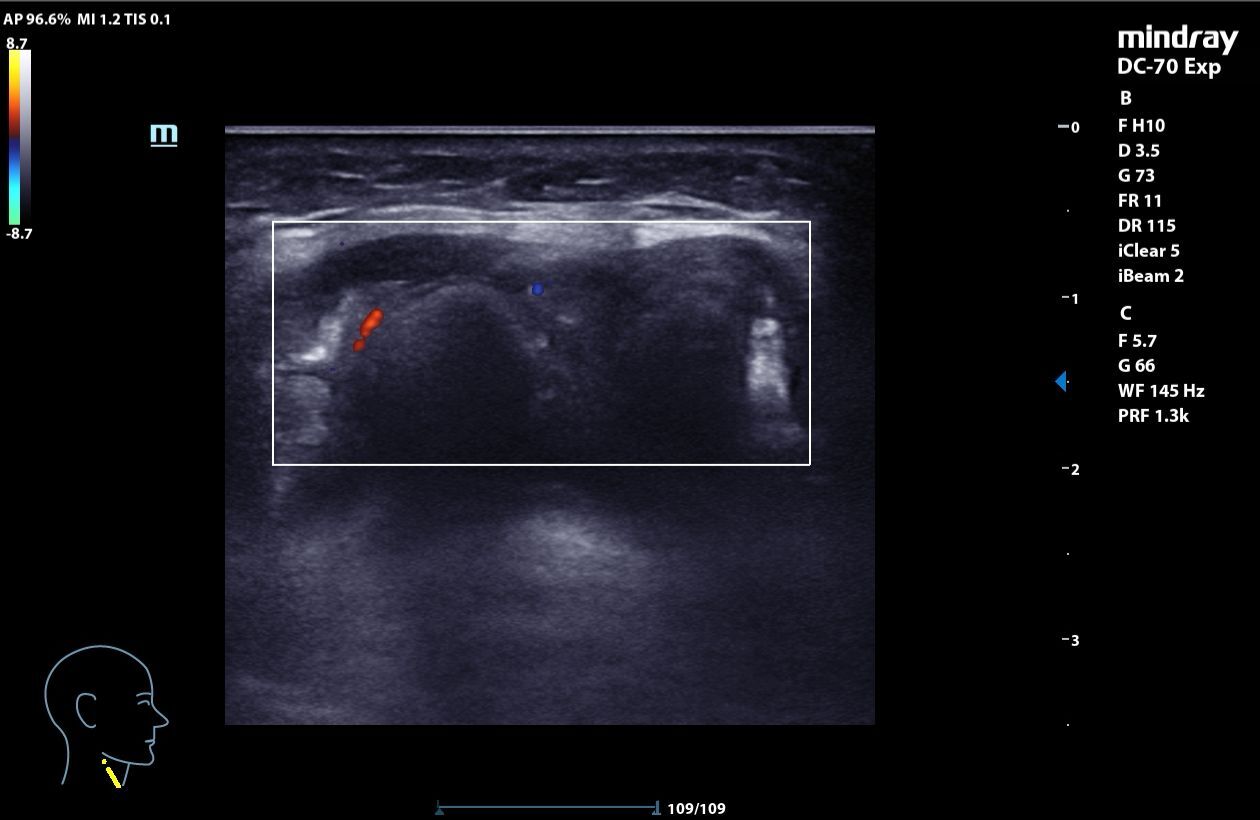

A nivel medial del cuello, por encima del cartílago cricoideo, masa heterogénea, mal delimitada, con calcificaciones internas que generan sombra acústica posterior, elementos hiperecogénicos y algunas zonas anecoicas con refuerzo posterior, con captación en Doppler. La lesión mide 3,06 x 1,48 x 2,78 cm y se mueve con la deglución. En relación con quiste tirogloso complicado o proceso neoformativo.